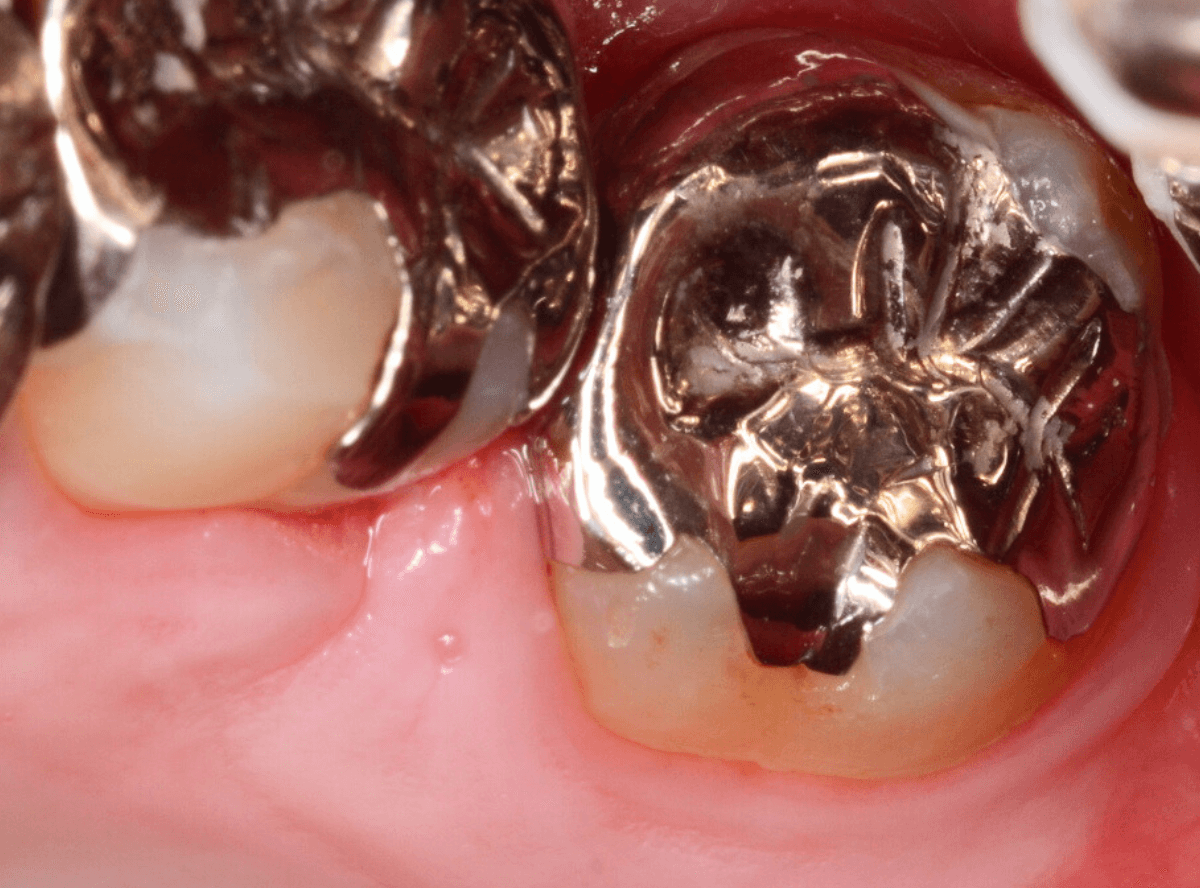

Case.14 インレーの下の歯肉まで広がった虫歯

「下の奥歯が噛むと痛む」という症状で来院された患者さんのケースです。

お口の中の状態を確認すると、奥歯の端に穴が開いているのが見えます。

ここかな?

レントゲン写真で確認します。

やはり、奥歯の端が大きな虫歯になっています。

青いラインが歯の神経、赤いラインが虫歯です。

レントゲン写真上では虫歯が神経まで達しているように見えます。

これは、神経を取らないとダメかもしれません。